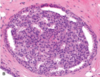

What is this an image of?

Normal breast